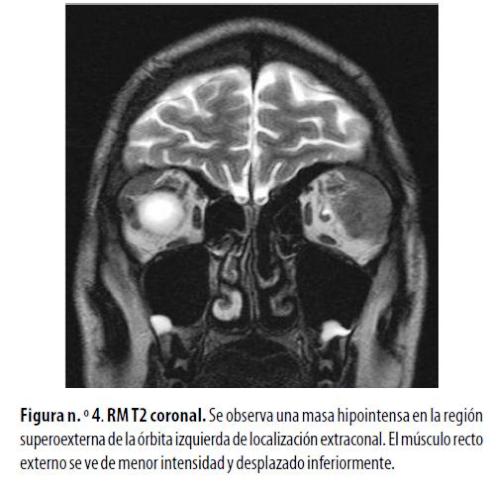

Hombre de 17 años con diagnóstico de LMA que afectaba el SNC. Presentó proptosis izquierda. En las imágenes ponderadas en T1 la RM demostró una lesión hipointensa y fusiforme en la región superoexterna de la órbita izquierda, que infiltraba el músculo recto externo. Presentó captación homogénea a la administración de gadolinio y se observó captación meníngea nodular en la región frontal. Había signos de reemplazo por grasa de la médula ósea de la calota craneana por infiltración mieloide (figura n.º 4) . Se le administraron radioterapia y quimioterapia y presentó mejoría en el primer año de tratamiento.